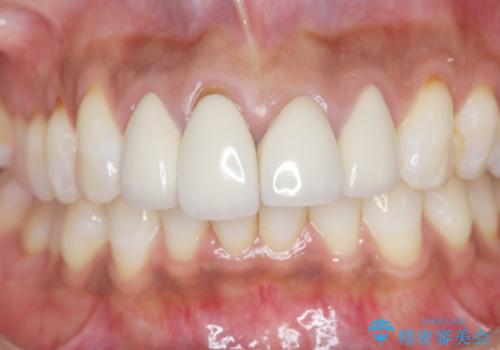

金属色の見える前歯 オールセラミックで審美治療

- 前歯のクラウンの見た目が不自然、歯の根元が見えたり金属色が気になるので改善したい、とセラミック治療を希望され来院されました。

歯肉の位置変化による審美障害を改善するため、オールセラミックジルコニアクラウンで再治療を行い審美性の改善を計画します。

見た目が自然になり、色調も天然の歯とおなじような透明感のある色調が再現され、大変喜んでいただくことができました。